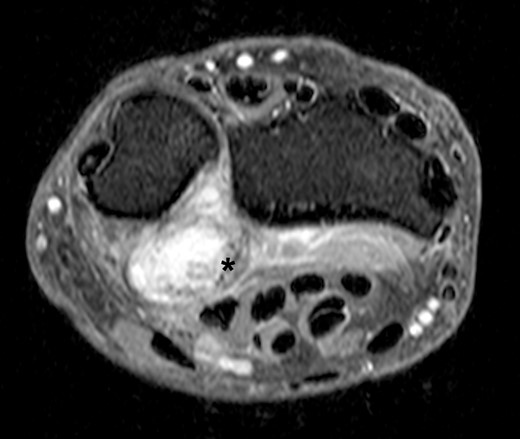

MRI scan revealed suspicion of ganglion cyst formation. The images (Figs 1 and 2) depicted a palmar-directed mass originating from the DRUJ with a transverse diameter measuring a maximum of 12 x 17 mm. The mass exhibited a predominant fluid isointense internal signal, accompanied by marginal signal depressions on T2-weighted sequence. These depressions within the suspected ganglion raised suspicion of diffuse-type tenosynovial giant cell tumor. The mass had contact to the flexor tendons at the level of the DRUJ. No pathological bone marrow edema was observed.

Axial slice of a fat suppressed PD Dixon—synovial capsular proliferation on the volar aspect of the DRUJ (asterix); the capsule is thickened, additionally evidence of hypointense internal structures aside the capsular proliferation.